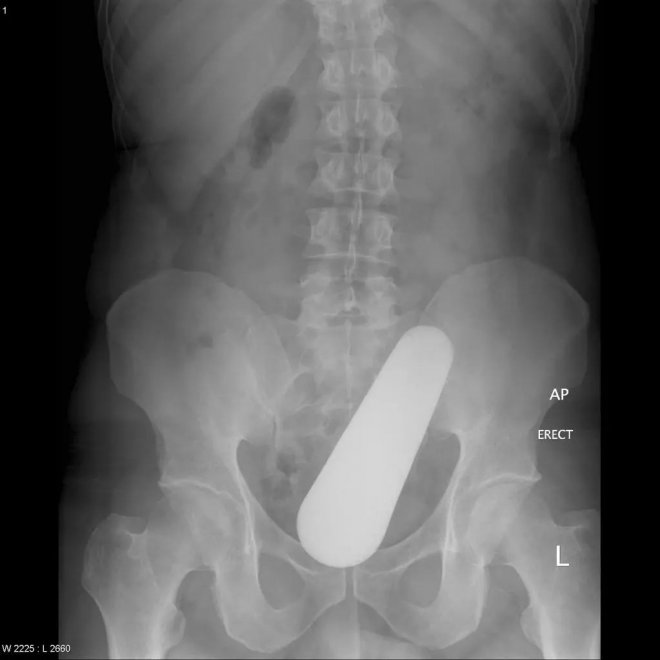

小胡瓜

19厘米長,頂端已經到了膽囊附近,這種病例非常罕見,使得醫生很納悶是怎麼把蔬菜塞進直腸的